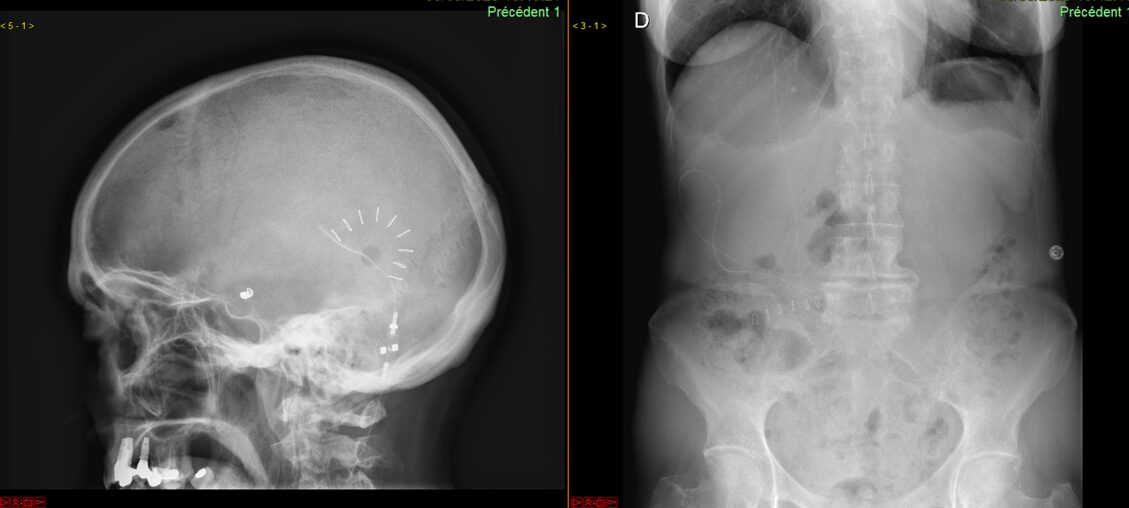

Un cathéter réglable est introduit dans les ventricules et connecté à la cavité abdominale (=dérivation ventriculo-péritonéale) ou au niveau du cœur dans l’atrium cardiaque droit (=dérivation ventriculo-atriale).

Dérivation ventriculo-péritonéale